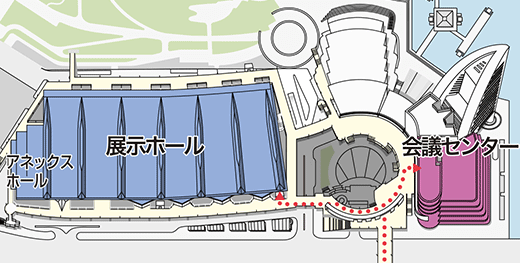

- パシフィコ横浜 会議センター3階 313+314

- パシフィコ横浜 会議センター1階 および アネックスホール

ITEM in JRC 2018 国際医用画像総合展 開催概要

- パシフィコ横浜 展示ホール